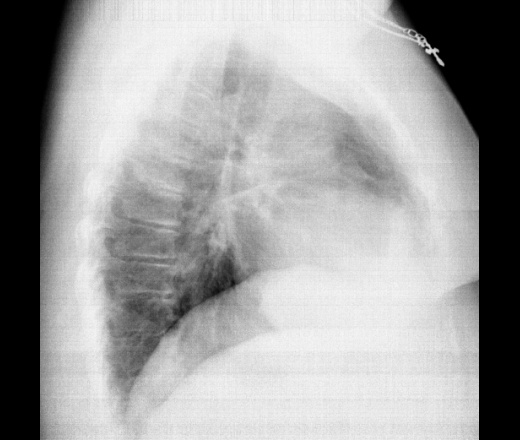

Пол пациента: Женский пол Тип патологии: Другое Область исследования: Грудная клетка и верхние дыхательные пути Методы исследования: Rg Женщина 30л. Диагностическая флюорография. За 4 ребром справа овальная тень? Дисковидный ателектаз? Ваше мнение коллеги? ID:78936 Цель публикации: Консультация Wed, 14/11/2018 - 21:14 #1 Игорь Ким Offline Last seen: 1 year 5 months ago Joined: 17.10.2014 - 17:30 Posts: 4672 Не ателектаз. Уплотнение добавочной междолевой. Wed, 14/11/2018 - 21:24 #2 И.Бондаренко Offline Last seen: 21 hours 43 min ago Joined: 13.09.2011 - 22:55 Posts: 9208 Игорь Ким wrote: Не ателектаз. Уплотнение добавочной междолевой. Возможно малый плеврит. Wed, 14/11/2018 - 21:37 #3 NIL Offline Last seen: 1 month 1 week ago Joined: 25.11.2013 - 20:50 Posts: 18208 Игорь Ким wrote: Уплотнение добавочной междолевой. +1 "Слушай всех, прислушивайся к немногим, решай сам".© Thu, 15/11/2018 - 06:21 #4 Оськин С.В. Offline Last seen: 2 years 4 weeks ago Joined: 07.04.2016 - 17:05 Posts: 1703 Коллеги, как вы оцениваете эту тень? У меня затрунение вызвала. Приложения:

Коллеги, как вы оцениваете эту тень? У меня затрунение вызвала.